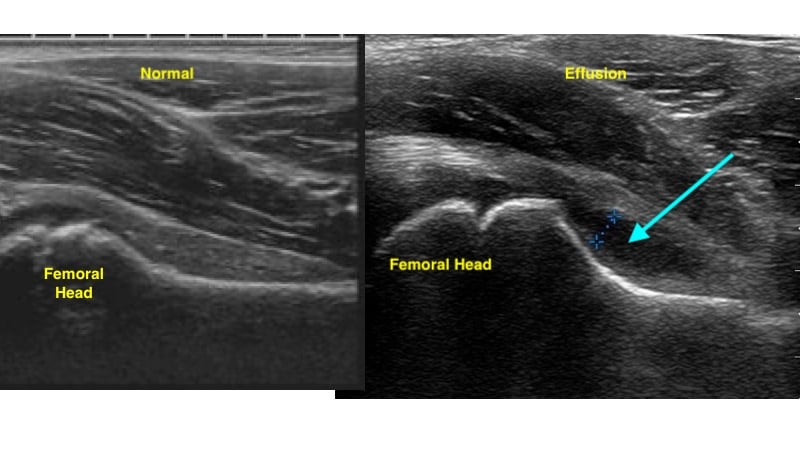

- Visualize the femoral neck extending to the femoral head

- Effusion is identified as a hypoechoic area along the femoral head/ neck within the hyperechoic capsule.5 (Fig. 7)

- Figure 7. Ultrasound demonstrating normal hip (left) and hip effusion (right)